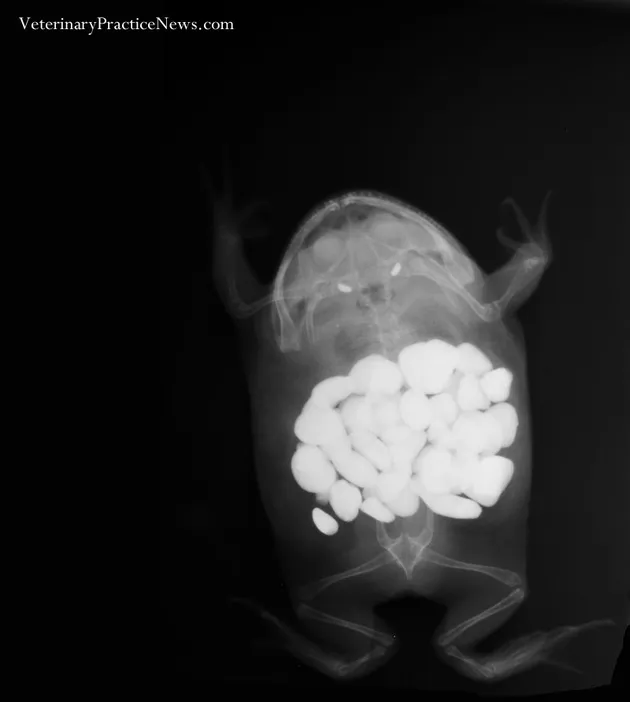

Seekor katak di Texas diketahui menelan batu kecil yang biasa digunakan sebagai ornamen. Tak tanggung-tanggung, katak ini menelan hingga 30 batu! Katak tersebut dibawa ke rumah sakit hewan Paws & Claws untuk dioperasi demi mengeluarkan batu-batu tersebut.

Hak Cipta: Veterinary Practice News